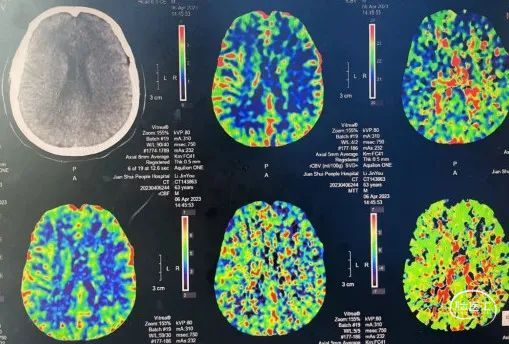

术前影像

头颅MRA示:左侧大脑中动脉M2段重度狭窄。

CTA进一步明确:左侧大脑中动脉M2重度狭窄。

头颅CTA:左侧大脑中动脉M1分叉后段局限性显影浅淡。双侧颈内动脉颅内段管壁稍毛糙,可见多发钙化斑块。左侧颈内动脉C6段轻度狭窄,右侧颈内动脉C6段轻-中度狭窄。双侧后交通动脉纤细。余头颈部血管未见明显异常改变。

颈部CTA:双侧颈动脉分叉少许混合性斑块,管腔未见狭窄。左侧椎动脉V3段局限性显影浅淡。主动脉弓、头臂干管壁少许钙化斑块。右锁骨下动脉管腔少许混合性斑块,管腔局限性中度狭窄。

头颅CTP:左侧大脑中动脉供血区灌注稍减低,以双侧颞叶为例,TTP(右侧22.6,左侧23.6)左侧较对侧稍延长;MTT(右侧4.9,左侧5.2),左侧较对侧稍延长;CBF(右侧25.1,左侧18.4),左侧较右侧降低;CBV(右侧1.9,左侧1.5),左侧较右侧稍减少。

双侧额叶见小点状稍低密度影。余颅内未见明确异常密度影,脑灰白质对比清晰,脑室无增大,脑沟、脑池稍增宽加深,中线结构居中。增强扫描未见异常强化。